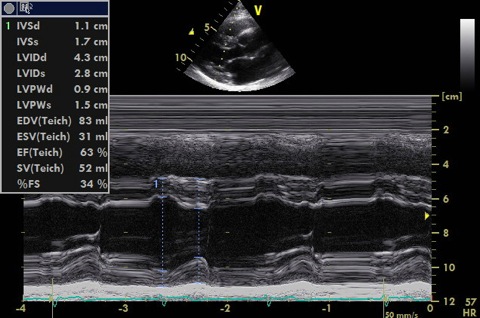

Just beyond tips of MV leaflets at 90 degrees to long axis of LV

- Measure septum, LV cavity, posterior wall in systole and diastole

- These can be measured from 2D if the ventricle is not at 90 to your scan line (which is frequently the case)